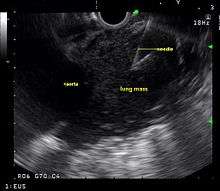

Endoscopic ultrasound (EUS) is an endoscopic technique where a miniaturized ultrasound probe is passed though the mouth into the upper gastrointestinal tract to investigate organs and structures close to the esophagus, stomach, or duodenum, such as the lung. In 1993, Wiersema published the first description of EUS to diagnose and stage lung cancer,[27] done by advancing a fine needle through the esophagus into adjacent lymph nodes. Numerous subsequent studies have shown this general methodology to be effective, very safe, minimally invasive, and very well tolerated. Given these advantages, many authorities think that EUS together with endobronchial ultrasound (EBUS) enhances lung cancer diagnosis and staging.[28]